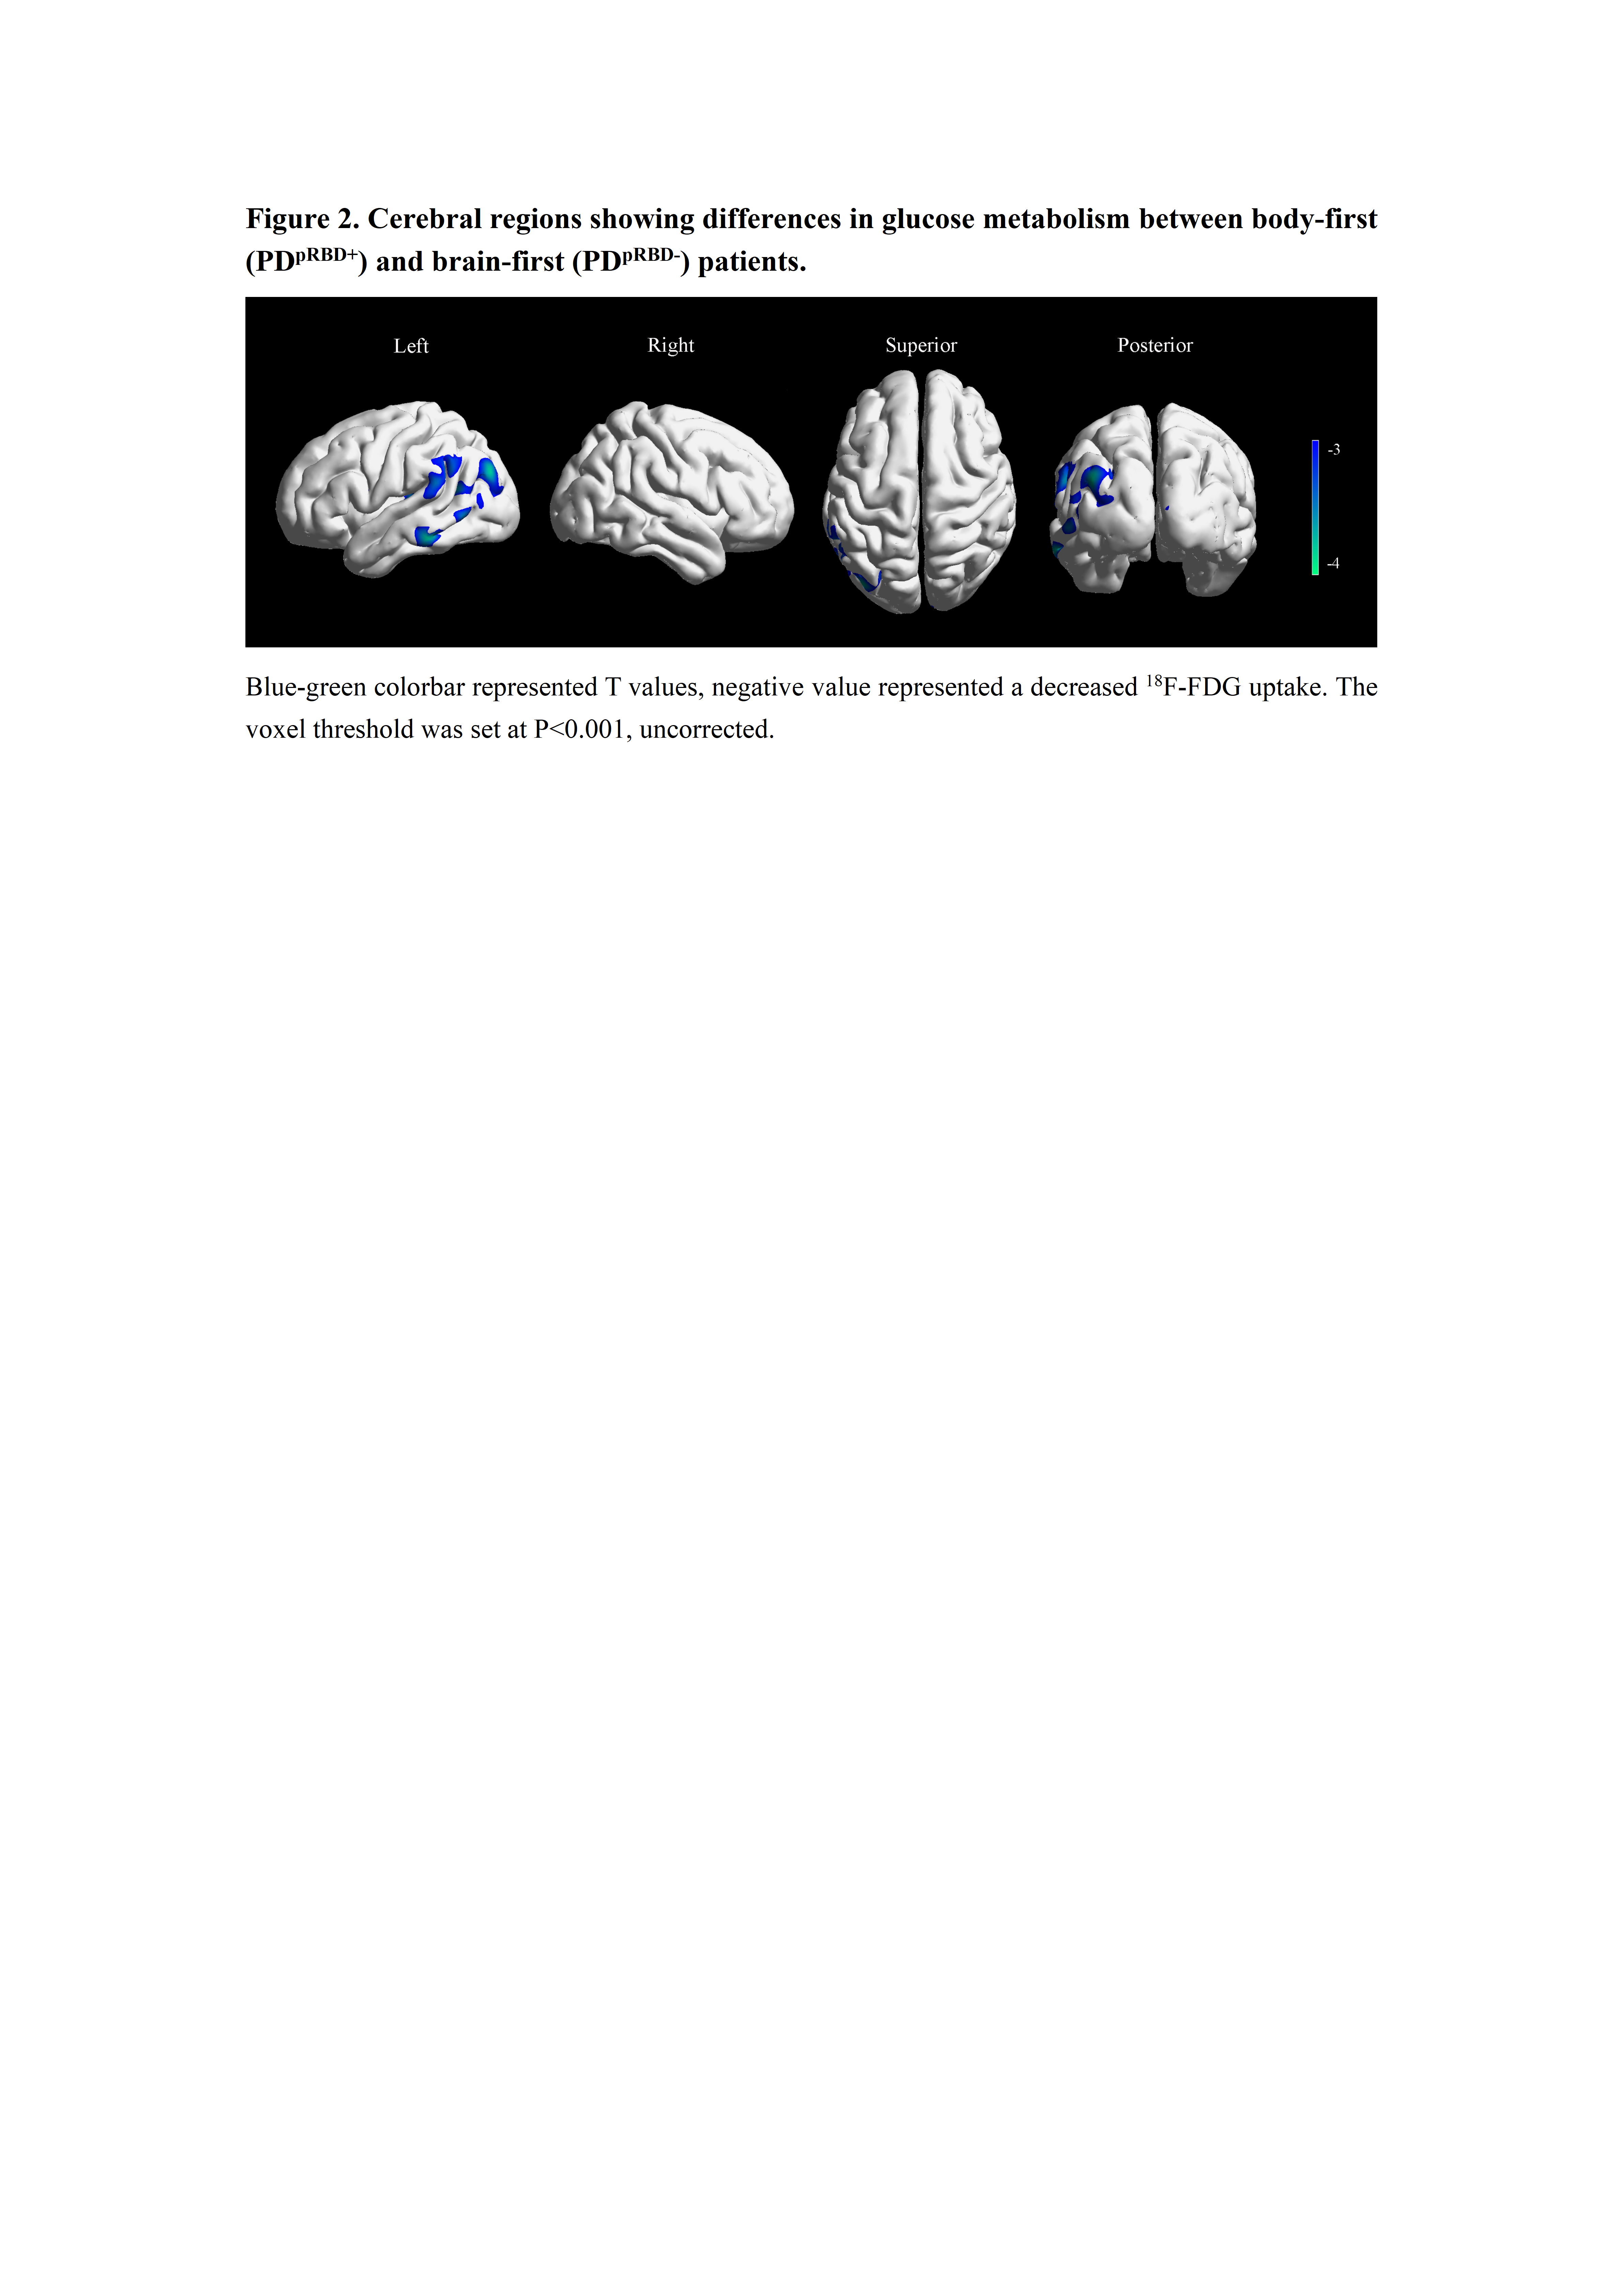

Results: The body-first group patients showed worse autonomic dysfunction (P=0.023) and lower quality of life (P=0.028) at baseline. Longitudinally, they showed faster motor progression (P=0.013) and greater decline in attention and working memory (P=0.003). Plasma GFAP (P<0.001) and NfL (P=0.042) were higher in the body-first group. Body-first patients showed reduced glucose metabolism in left middle temporal, bilateral middle occipital, and left inferior parietal gyrus (P<0.001). In the brain-first group, plasma GFAP was positively correlated with substantia nigra metabolism (r=0.38, P=0.003) and negatively with parietal cortex metabolism (r=-0.42, P<0.001). Plasma NfL was positively correlated with cerebellar metabolism (r=0.35, P=0.008) and negatively with anterior cingulate cortex metabolism (r=-0.41, P=0.001). No significant correlations were observed in the body-first group.

Figure 2